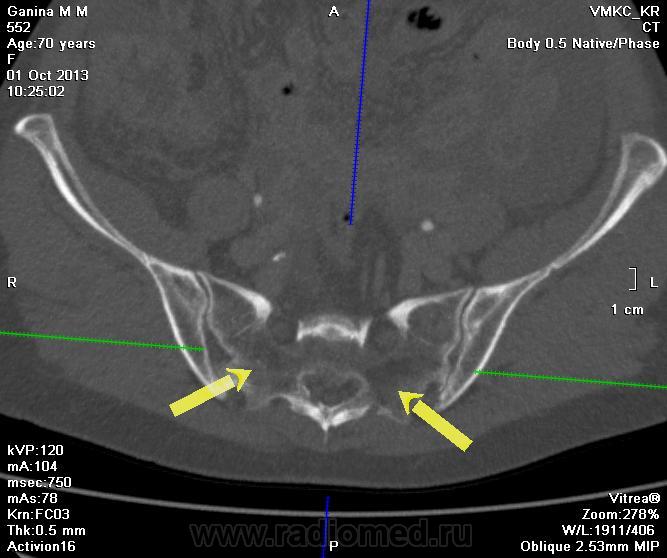

Сегодня смотрел пациентку с подозрением на c-r яичников. Подскажите: данные изменения в костях - деструкция? Отмеченные гиподенсные участки плотностью -80 -30 HU.

Остепорозные дела , на метастазы не тянет из-за "нейтральности" по отношению к стуктуре.Т.е. нет четких признаков деструкции структуры, нет четких бластолитических изменений.

Ну, ладно, смотрите сами: литический метастаз - это не просто участок разрежения костной структуры, это кусок опухоли. Так что, должен быть мягкотканный компонент.

Не очень похоже на метатстаза, не такие они, более четко очерчены. В мягоктканном окне еще посмотрИте.

Согласен с Андреем Юрьевичем. При mts должен быть мягкотканный компонент. Минусовая плотность очагов говит сама за себя - это очаги жировой дегенерации красного костного мозга,  т.е. обычное дело при остеопорозе. Я бы больше ничего из исследований для крестца не назначал.

По теме - вряд ли мета. Скорее возрастные изменения.